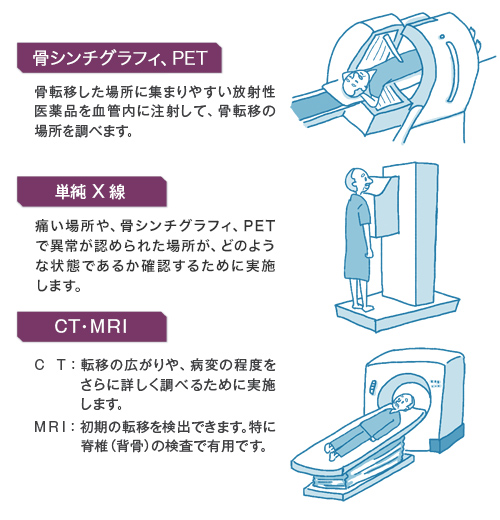

前立腺がんの検査 画像検査 Ct Mri 骨シンチグラフィ で何がわかる

検査の流れ 50歳を過ぎたら注意 前立腺がん 患者 ご家族の皆様

確定診断までの流れ がんの治療法 詳しく知りたい 前立腺がん

確定診断までの流れ がんの治療法 詳しく知りたい 前立腺がん